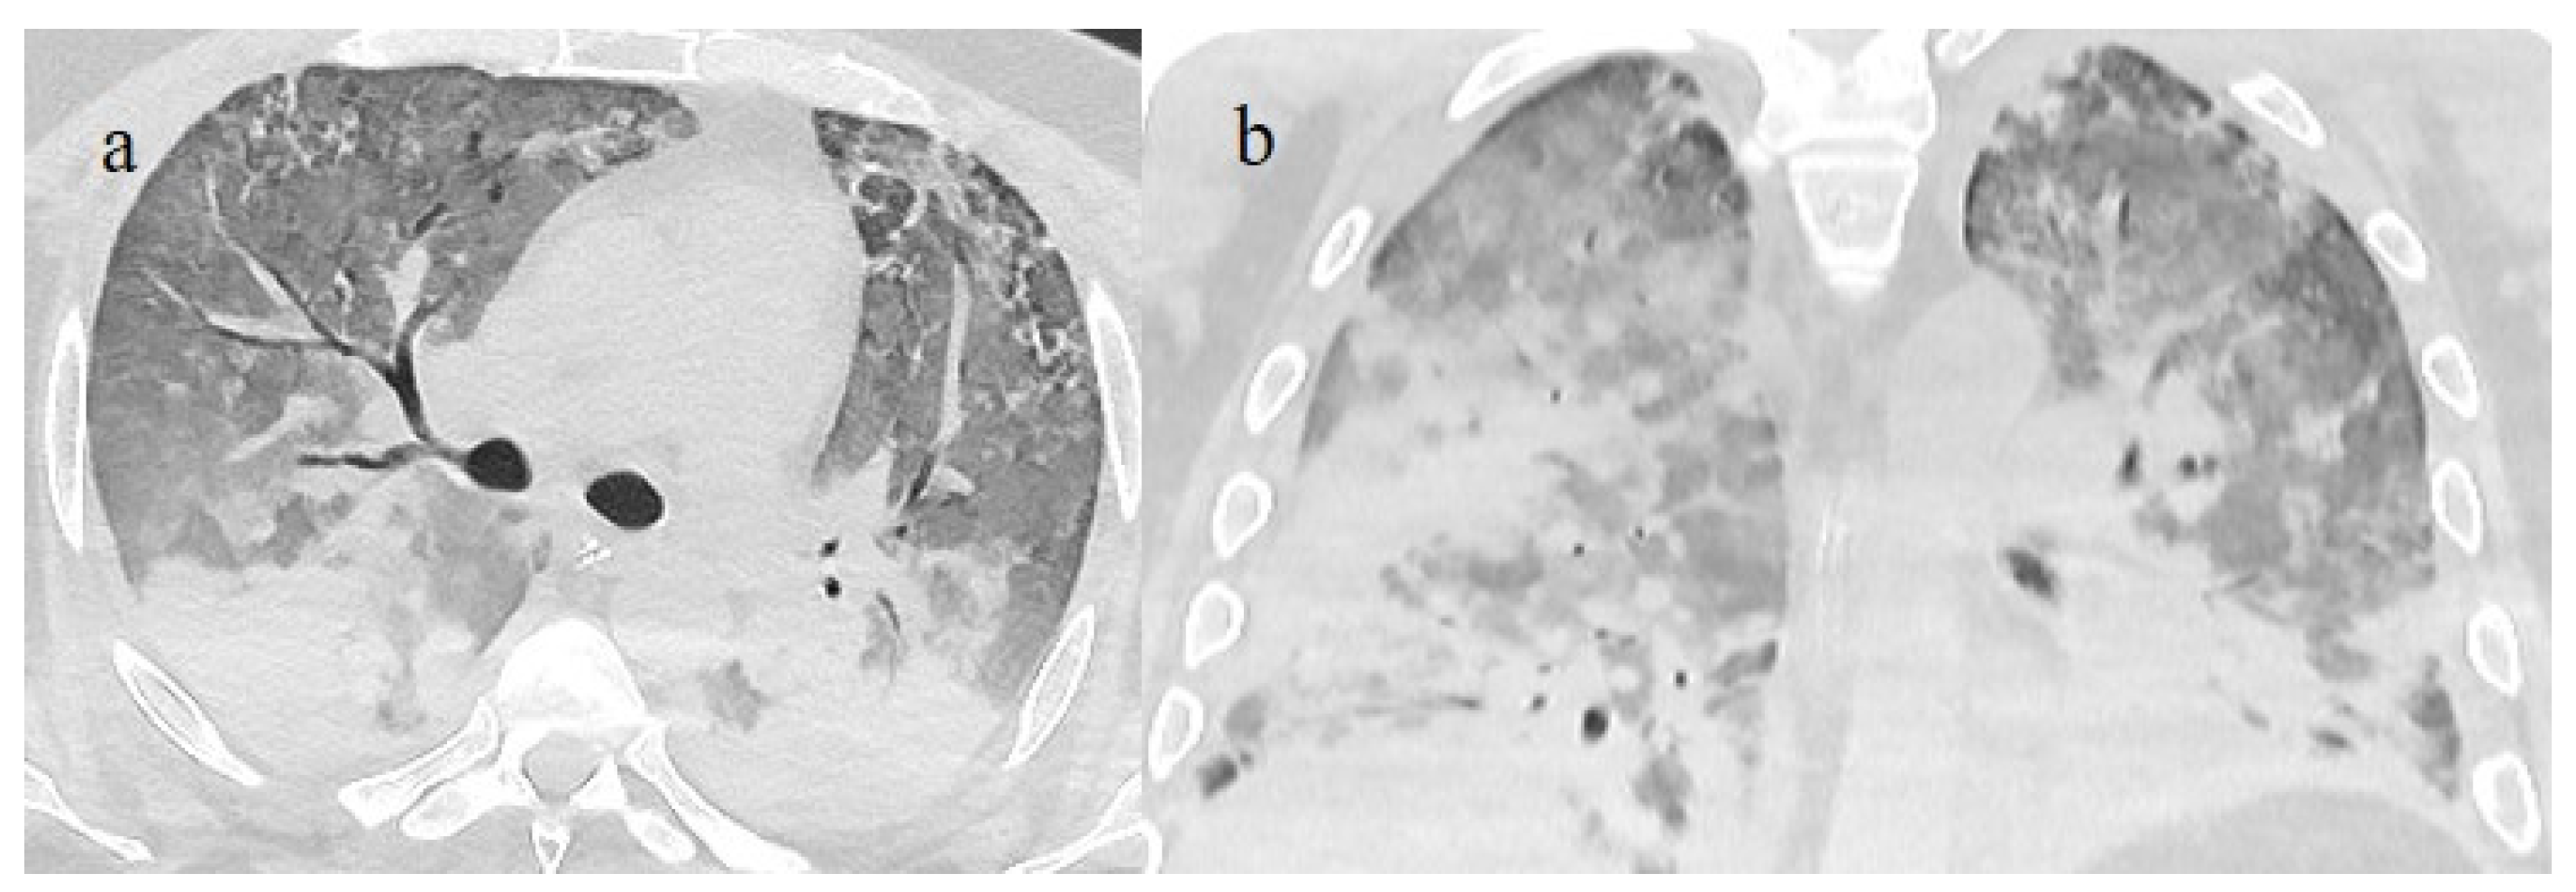

| Typical Appearance | GGOs with a crazy-paving pattern and consolidations in a peripheral and posterior or central-peripheral distribution; multilobar involvement; vascular enlargement, the halo and reversed halo sign; subpleural and parenchymal bands; and architectural distortion. They were predominant since the Delta wave. |

| Indeterminate Appearance | GGOs and consolidations with a unilateral, central, or upper-lobe distribution. |

| Atypical Appearance | Lobar consolidation, lung nodules or masses, miliary patterns, tree-in-bud patterns, cavitation, pleural effusion, central distribution, and lymphadenopathy. Atypical appearances were predominant during the Omicron waves. |

| Typical appearance | From the wild-type to the Delta variant. | Askani et al., 2022 [67] | The Delta variant presented more frequent typical features with more extensive lung involvement than the Omicron variant. The Omicron variant was more frequently associated with the absence of pneumonia. |

| Inui et al., 2021 [68] | Typical findings were characteristic of the wild type to the Delta variant. GGOs with consolidation and repair changes were more frequent in the Delta variant. The Delta variant also showed more rapid pneumonia progression than the wild-type and Alpha variants. | ||

| Ito et al., 2022 [54] | Peripheral GGO distributions were more frequent in the Alpha and Delta variants than the Omicron variant. | ||

| Kirka et al., 2022 [27] | Typical features were found in 40.8% of patients with the wild-type variant and 1.7% of patients with the Omicron variant. | ||

| Lee et al., 2023 [28] | Typical CT patterns were more frequent in the Delta group (76%) than in those with the Omicron variant (42%). | ||

| Yang et al., 2022 [78] | Of patients with the Alpha variant, 86.84% presented typical COVID-19 pneumonia CT features. | ||

| Yoon et al., 2023 [69] | Only 32% of patients with the Omicron variant presented typical findings, compared with 57% of the Delta variant cases. | ||

| Indeterminate appearance | Omicron variant | Ito et al., 2022 [54] | Cluster-like GGOs in the Omicron wave. |

| Atypical appearance | Omicron Variant | Hang et al., 2023 [75] | Patients infected with the Omicron variant presented a significantly higher prevalence of nodules, tree-in-bud patterns, and halo signs than patients with the original strain. |

| Ito et al., 2022 [54] | Prevalence of non-peripheral distribution with random distribution during the Omicron wave. | ||

| Lee et al., 2023 [28] | Peribroncovascular pneumonia with the Omicron variant and lower rates of severe pneumonia than the Delta variant. | ||

| Tsakok et al., 2023 [77] | Patients with an Omicron infection presented a greater frequency of bronchial wall thickening but less severe disease compared with the Delta variant. | ||

| Yang et al., 2022 [78] | Only 1.3% of patients infected with the Omicron variant had foci of pneumonia, and the GGOs were unilateral and centrilobular. | ||

| Yoon et al., 2023 [69] | Peribroncovascular GGOs or centrolobular foci during the Omicron wave with less extensive pneumonia. |